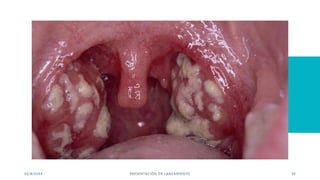

EXISTE DIFERENTES

ENFERMEDADES

TRASMITIDAS POR SALIVA